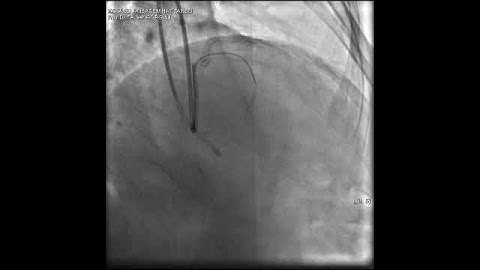

Aortic dissection and radial rupture during retrograde CTO PCI: Management of complications VİDEO 15